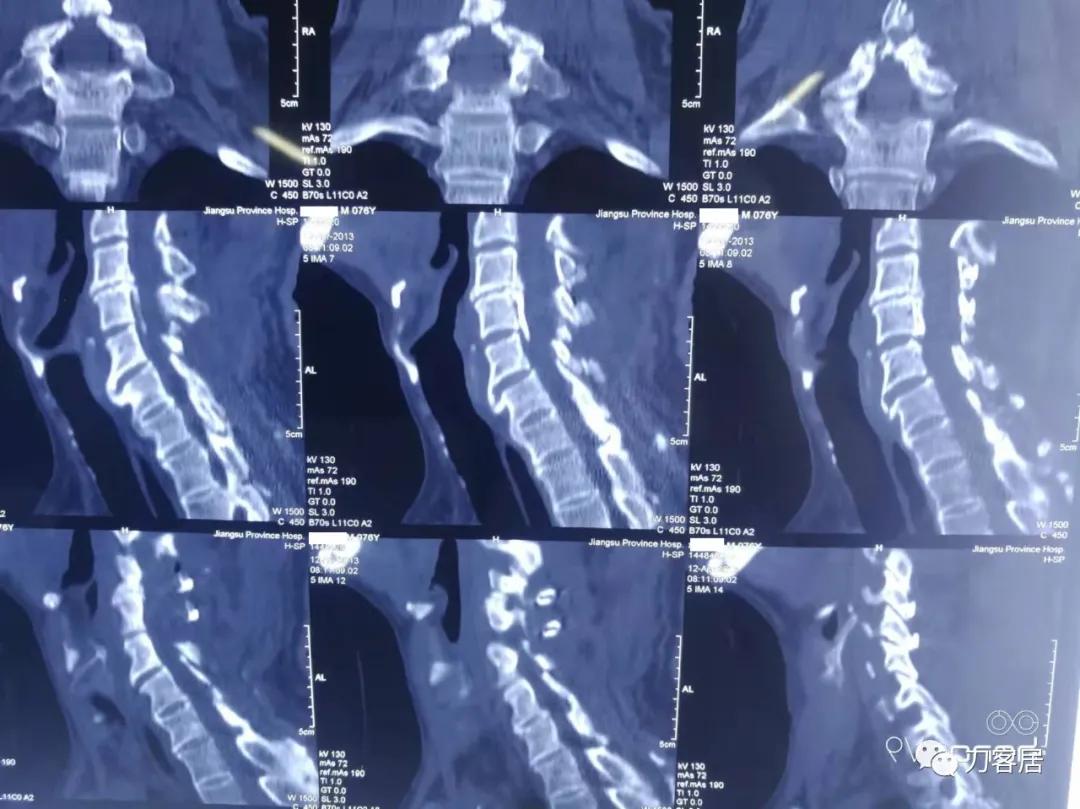

图19. 2012年12月6日颈椎椎管成形术前三维CT重建

图20. 2013年4月12日术后颈椎三维CT重建